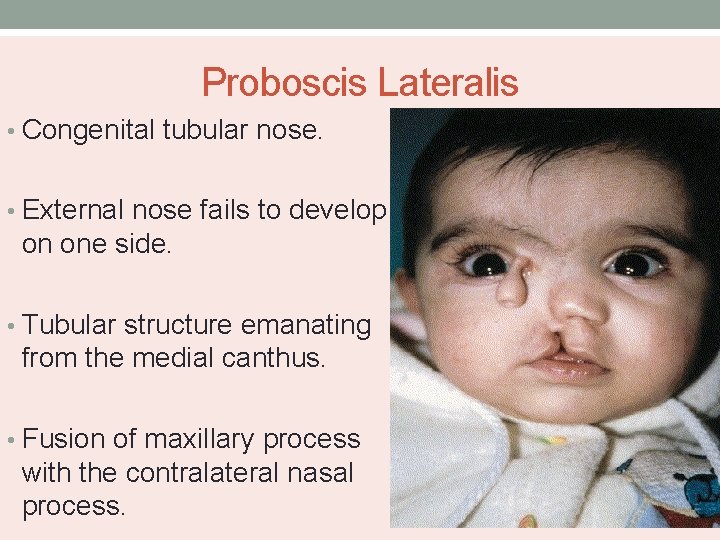

Proboscis Lateralis • Congenital tubular nose. • External nose fails to develop on one side. • Tubular structure emanating from the medial canthus. • Fusion of maxillary process with the contralateral nasal process.

• Characterized by absence of nasal cavity and PNS on one side. • Nasolacrimal duct ends blindly. • Associated with microphthalmus, coloboma and arachnoid cysts. • Rerouting of nasolacrimal duct and excision of tubular deformity